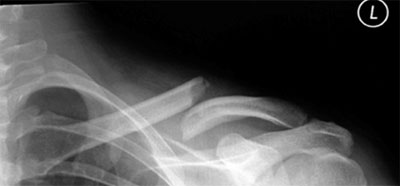

У детей переломы ключицы чаще бывают поднадкостничными, у взрослых — со смещением. Чаще переломы ключицы локализуются в средней трети или на границе средней и дистальной трети. Переломы происходят в результате падения на вытянутую руку, локоть, наружную поверхность плеча или при непосредственной травме ключицы. Близость сосудисто-нервного пучка обусловливает возможность его повреждения и той или иной степени, что требует обязательного обследования больного. Реже наблюдаются переломы акромиального конца ключицы, которые манифестируют вывихи ключицы в акромиально-ключичном сочленении.

При переломах ключицы у взрослых заметна не только гематома и припухлость, но и деформация, обусловленная смещением отломков: надплечье укорачивается по ширине и опускается. При пальпации определяется характер смещения костных отломков, который, как правило, типичен: проксимальный отломок смещается кверху и кзади, дистальный — книзу и кпереди. На рентгенограмме подтверждается характер смещения.